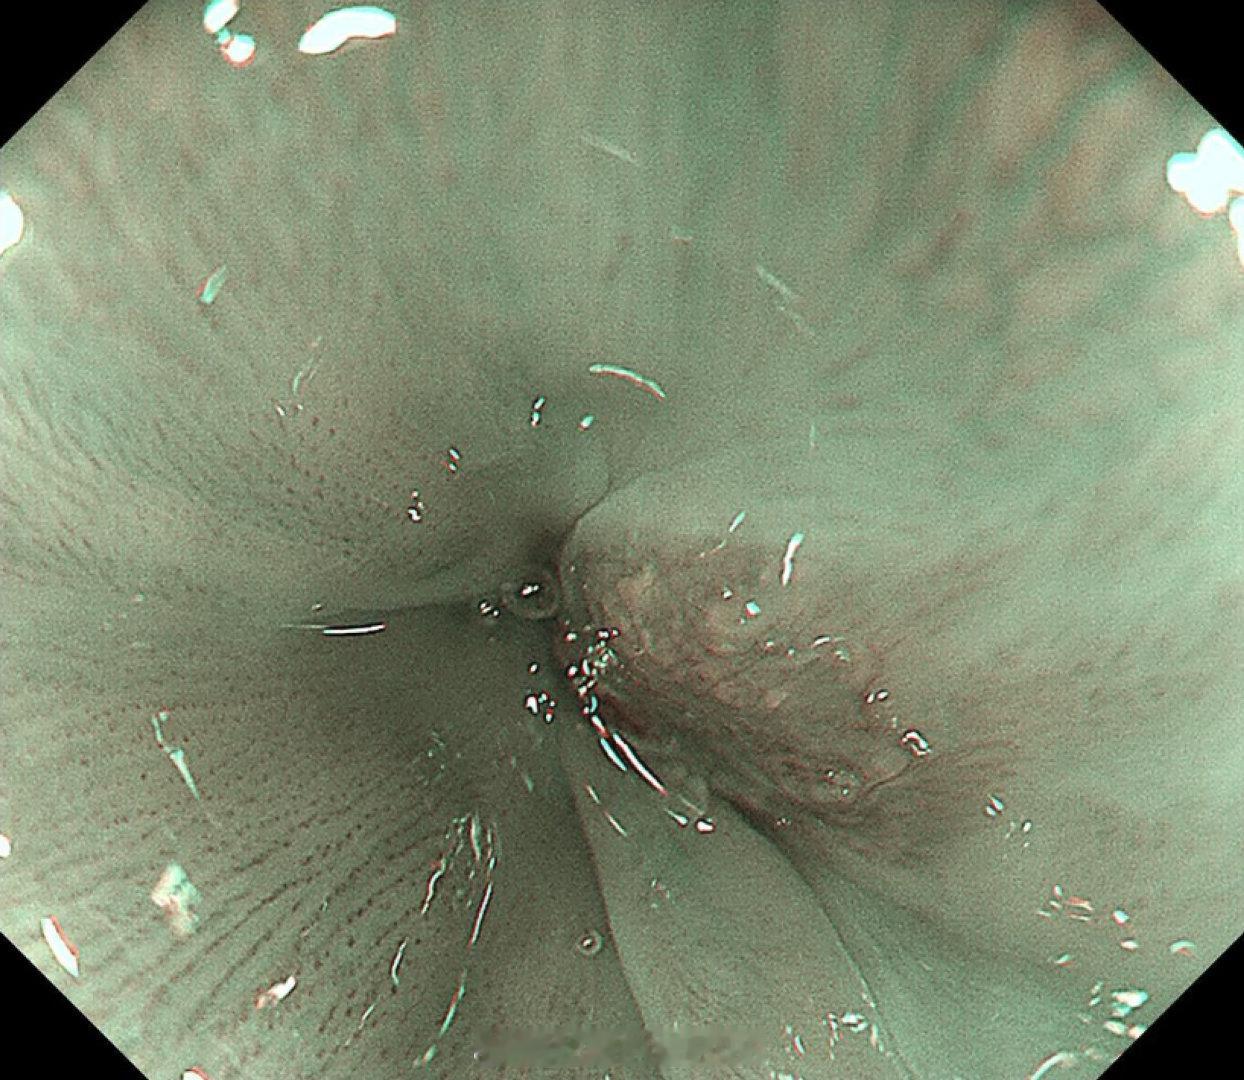

这是个兄弟医院做的内镜发现有贲门病灶,老人体型腹型肥胖很典型,返流持续那么多年导致的Barrett食管癌风险肯定是最高的,她女婿找我精查会诊了一次,我看着病灶虽小,但是有点僵硬,感觉已经到了黏膜下的barrett食管癌,但是他们都想尝试切除看看浸润深度,诊断性esd实施后黏膜下550微米,一般来说这地方超过500微米已经是sm2,淋巴结转移风险急剧加大了,后面就要纠结要不要追加外科手术,但是这个手术做了生活质量会相当不好。所以这种癌的最好措施是预防,发现非常困难,往往一发现就是深了。腹型肥胖的人群减重以减少返流是很重要的。